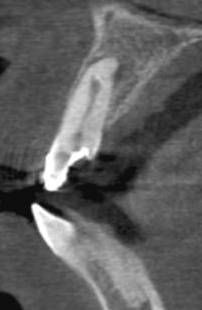

#7 referred with a separated file/internal resorption/calcification/apical split

> History of trauma and a I/O sinus present

Referring doctor had attempted an endo and separated an instrument

> Radiograph reveals

– Separated file lying horizontal in the internal resorptive defect

– A calcified mass of dentin within the resorptive defect

– An additional Canal present exiting laterally ?

PA lesion

> CBCT findings

No communication of internal resorption externally.

A sharp palatal curve of the root apically.